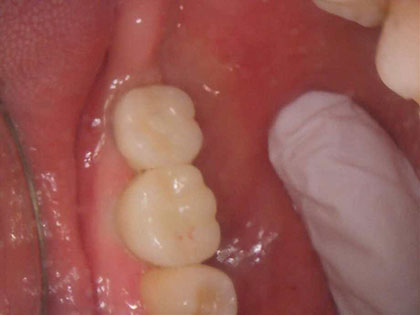

左下奥歯6、7番目にインプラント治療を行った症例

左下が腫れたり、噛むと痛いとの事で来院され、インプラント治療を希望された患者様の症例になります